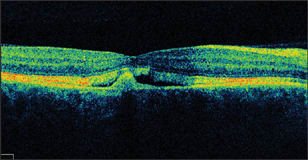

Optical coherence tomography (OCT) scans showed a well-defined material accumulation underneath the RPE in the right eye, with more pronounced cystic changes in the left eye (Figure 2).

Figure 2. OCT images of both eyes showing a subretinal pigment epithelium conical mound of moderately reflective material in the right eye (left scan) and a larger cystic space in the left eye (right scan).